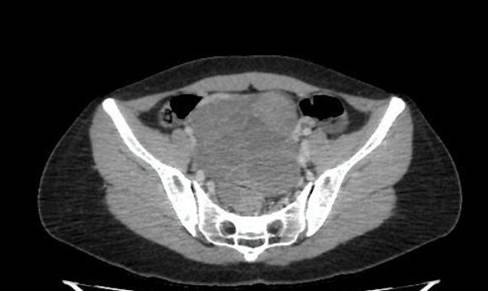

Paciente do sexo feminino, 35 anos, previamente hígida, gesta dois, para um, aborto um, com histórico de abortamento espontâneo há um ano. Queixava-se de dor de forte intensidade em baixo ventre e dispareunia de profundidade. Realizada ultrassonografia transvaginal (USG-TV), em janeiro de 2019, com visualização de coleção anexial heterogênea em ovário esquerdo medindo 7,4 x 5,4 x 8,4 cm, foi levantada a hipótese de cisto de corpo lúteo pós-aborto, prescrito acetato de medroxiprogesterona, sem melhora. Uma nova USG-TV foi solicitada em três meses, evidenciando permanência da massa anexial à esquerda, com projeção ao fundo de saco posterior. Por conta da expansividade da lesão, foram realizadas endoscopia digestiva alta e colonoscopia, esta última apontando uma lesão ulcerovegetante em junção retossigmoide, cuja biópsia revelou adenocarcinoma moderadamente diferenciado, ulcerado, infiltrando a lâmina própria. No momento do diagnóstico, a paciente referia perda ponderal de 3 kg na última semana e episódios prévios de hematoquezia, antes associados com doença hemorroidária. Posteriormente, foram revelados possíveis implantes neoplásicos em tomografia computadorizada (TC) de abdome e pelve: uma lesão hipodensa no fígado, além de lesão pélvica cística (Figura 1) — caracterizada como tumor de Krukenberg. Após duas semanas do diagnóstico inicial, optou-se, em fevereiro de 2019, pela realização de retossigmoidectomia com linfadenectomia, salpingo-oforectomia bilateral, além da ressecção de um implante peritoneal em fundo de Saco de Douglas, recebendo, com as peças cirúrgicas obtidas, o estadiamento patológico pT4apN2bpM1c, com margens de ressecção cirúrgica livres de neoplasia. Foi feita a execução do perfil molecular por pirosequenciamento, resultante em KRAS e NRAS de tipo selvagem, painel de câncer hereditário com ausência de variante patogênica e pesquisa de instabilidade microssatélite negativa com um único achado de variante de significado clínico incerto (VUS) no gene BLM. Após a realização de 11 ciclos de quimioterapia adjuvante quinzenalmente entre março e agosto de 2019 com protocolo FOLFOX (ácido folínico, 5-fluorouracil e oxaliplatina) + cetuximabe, houve resposta parcial detectada pela remanescência de metástases hepáticas na ressonância magnética (RM) de abdome.

Figura 1. (31/01/2019): Volumosa lesão pélvica de aspecto cístico multiloculado, medindo aproximadamente 12,0 x 11,1 x 9,2 cm. Mantém íntimo contato com a parede anteroinferior do retossigmoide, sem plano de clivagem evidente ao método